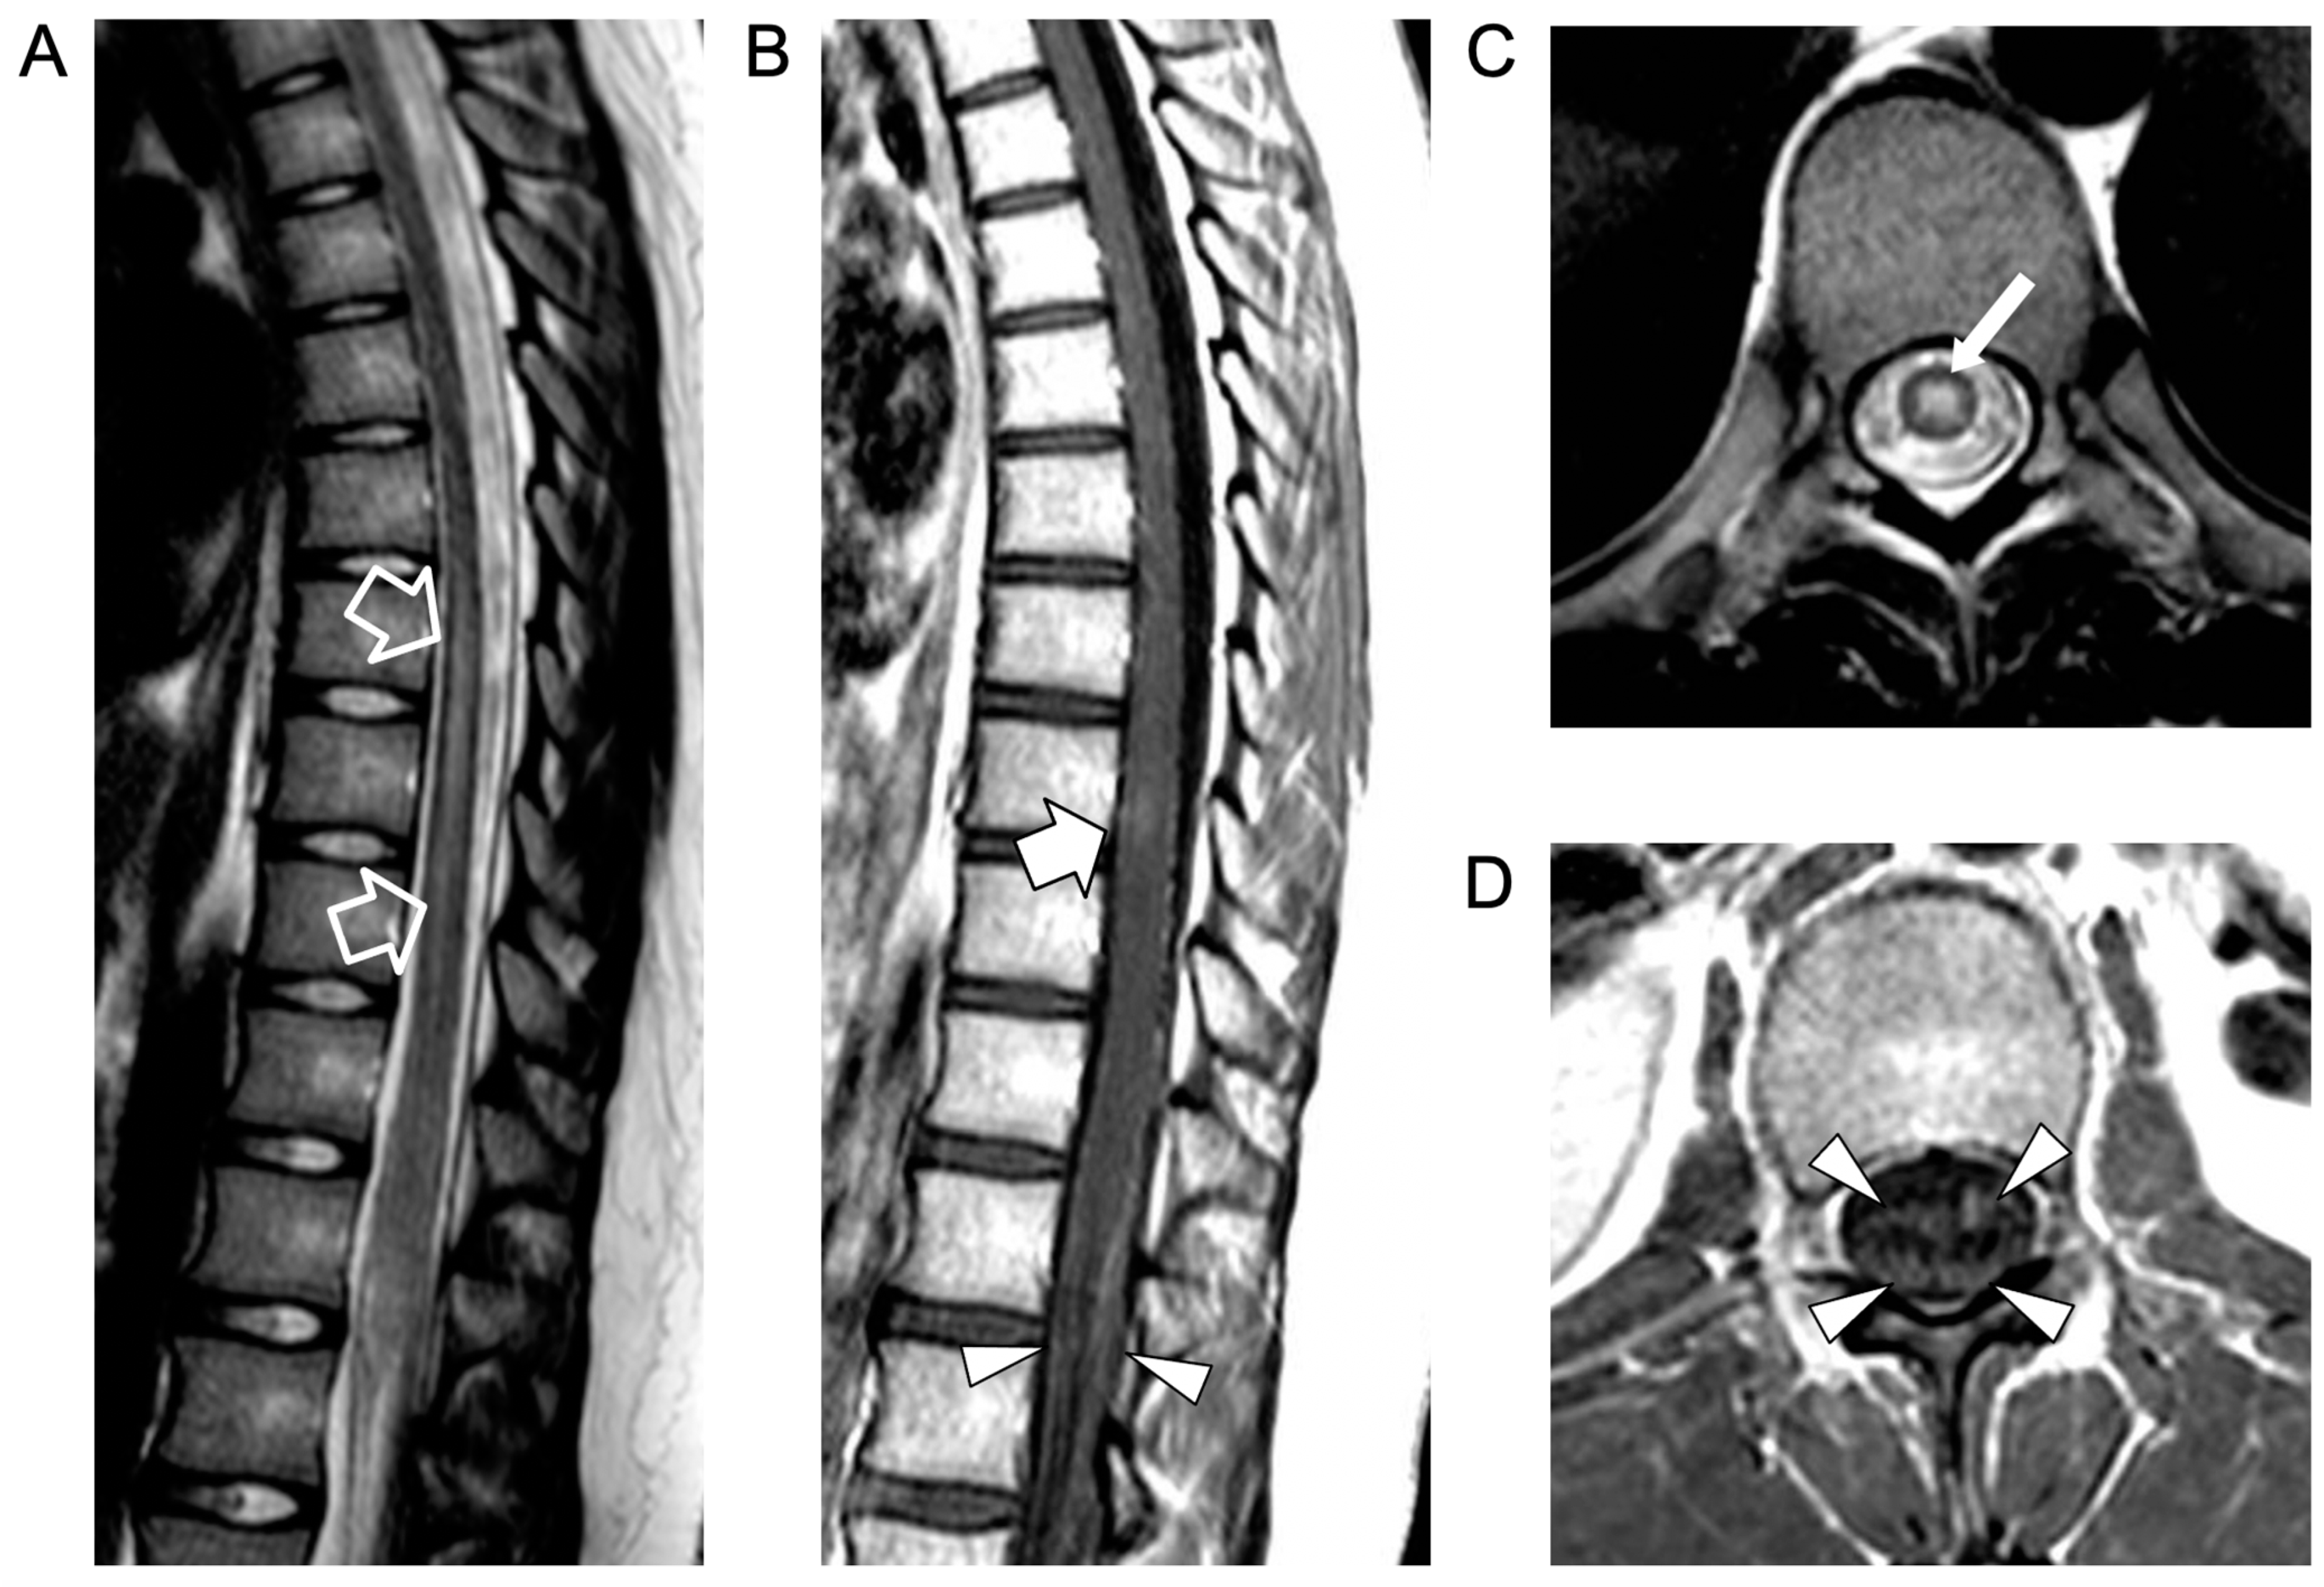

An urgent spinal magnetic resonance imaging (MRI) scan showed acute transverse myelitis extending from D7 to D10, associated with contrast enhancement of the anterior and posterior roots of the cauda equina, indicative of myeloradiculitis (Figure 1).

Figure 1.

Contrast-enhanced spinal MRI performed at clinical onset. Sagittal T2-weighted (A) and post-contrast T1-weighted (B) images; axial T2-weighted (C) and post-contrast T1-weighted (D) images. There is a T2 hyperintensity in the central portion of the spinal cord (empty arrows in (A) and thin arrow in (C)) in keeping with an acute transverse myelitis extending from D7 to D9, associated with a faint area of contrast enhancement at the D8 level (thick arrow). Note the contrast enhancement of the anterior and posterior cauda equina nerve roots (arrowheads) indicative of myeloradiculitis.